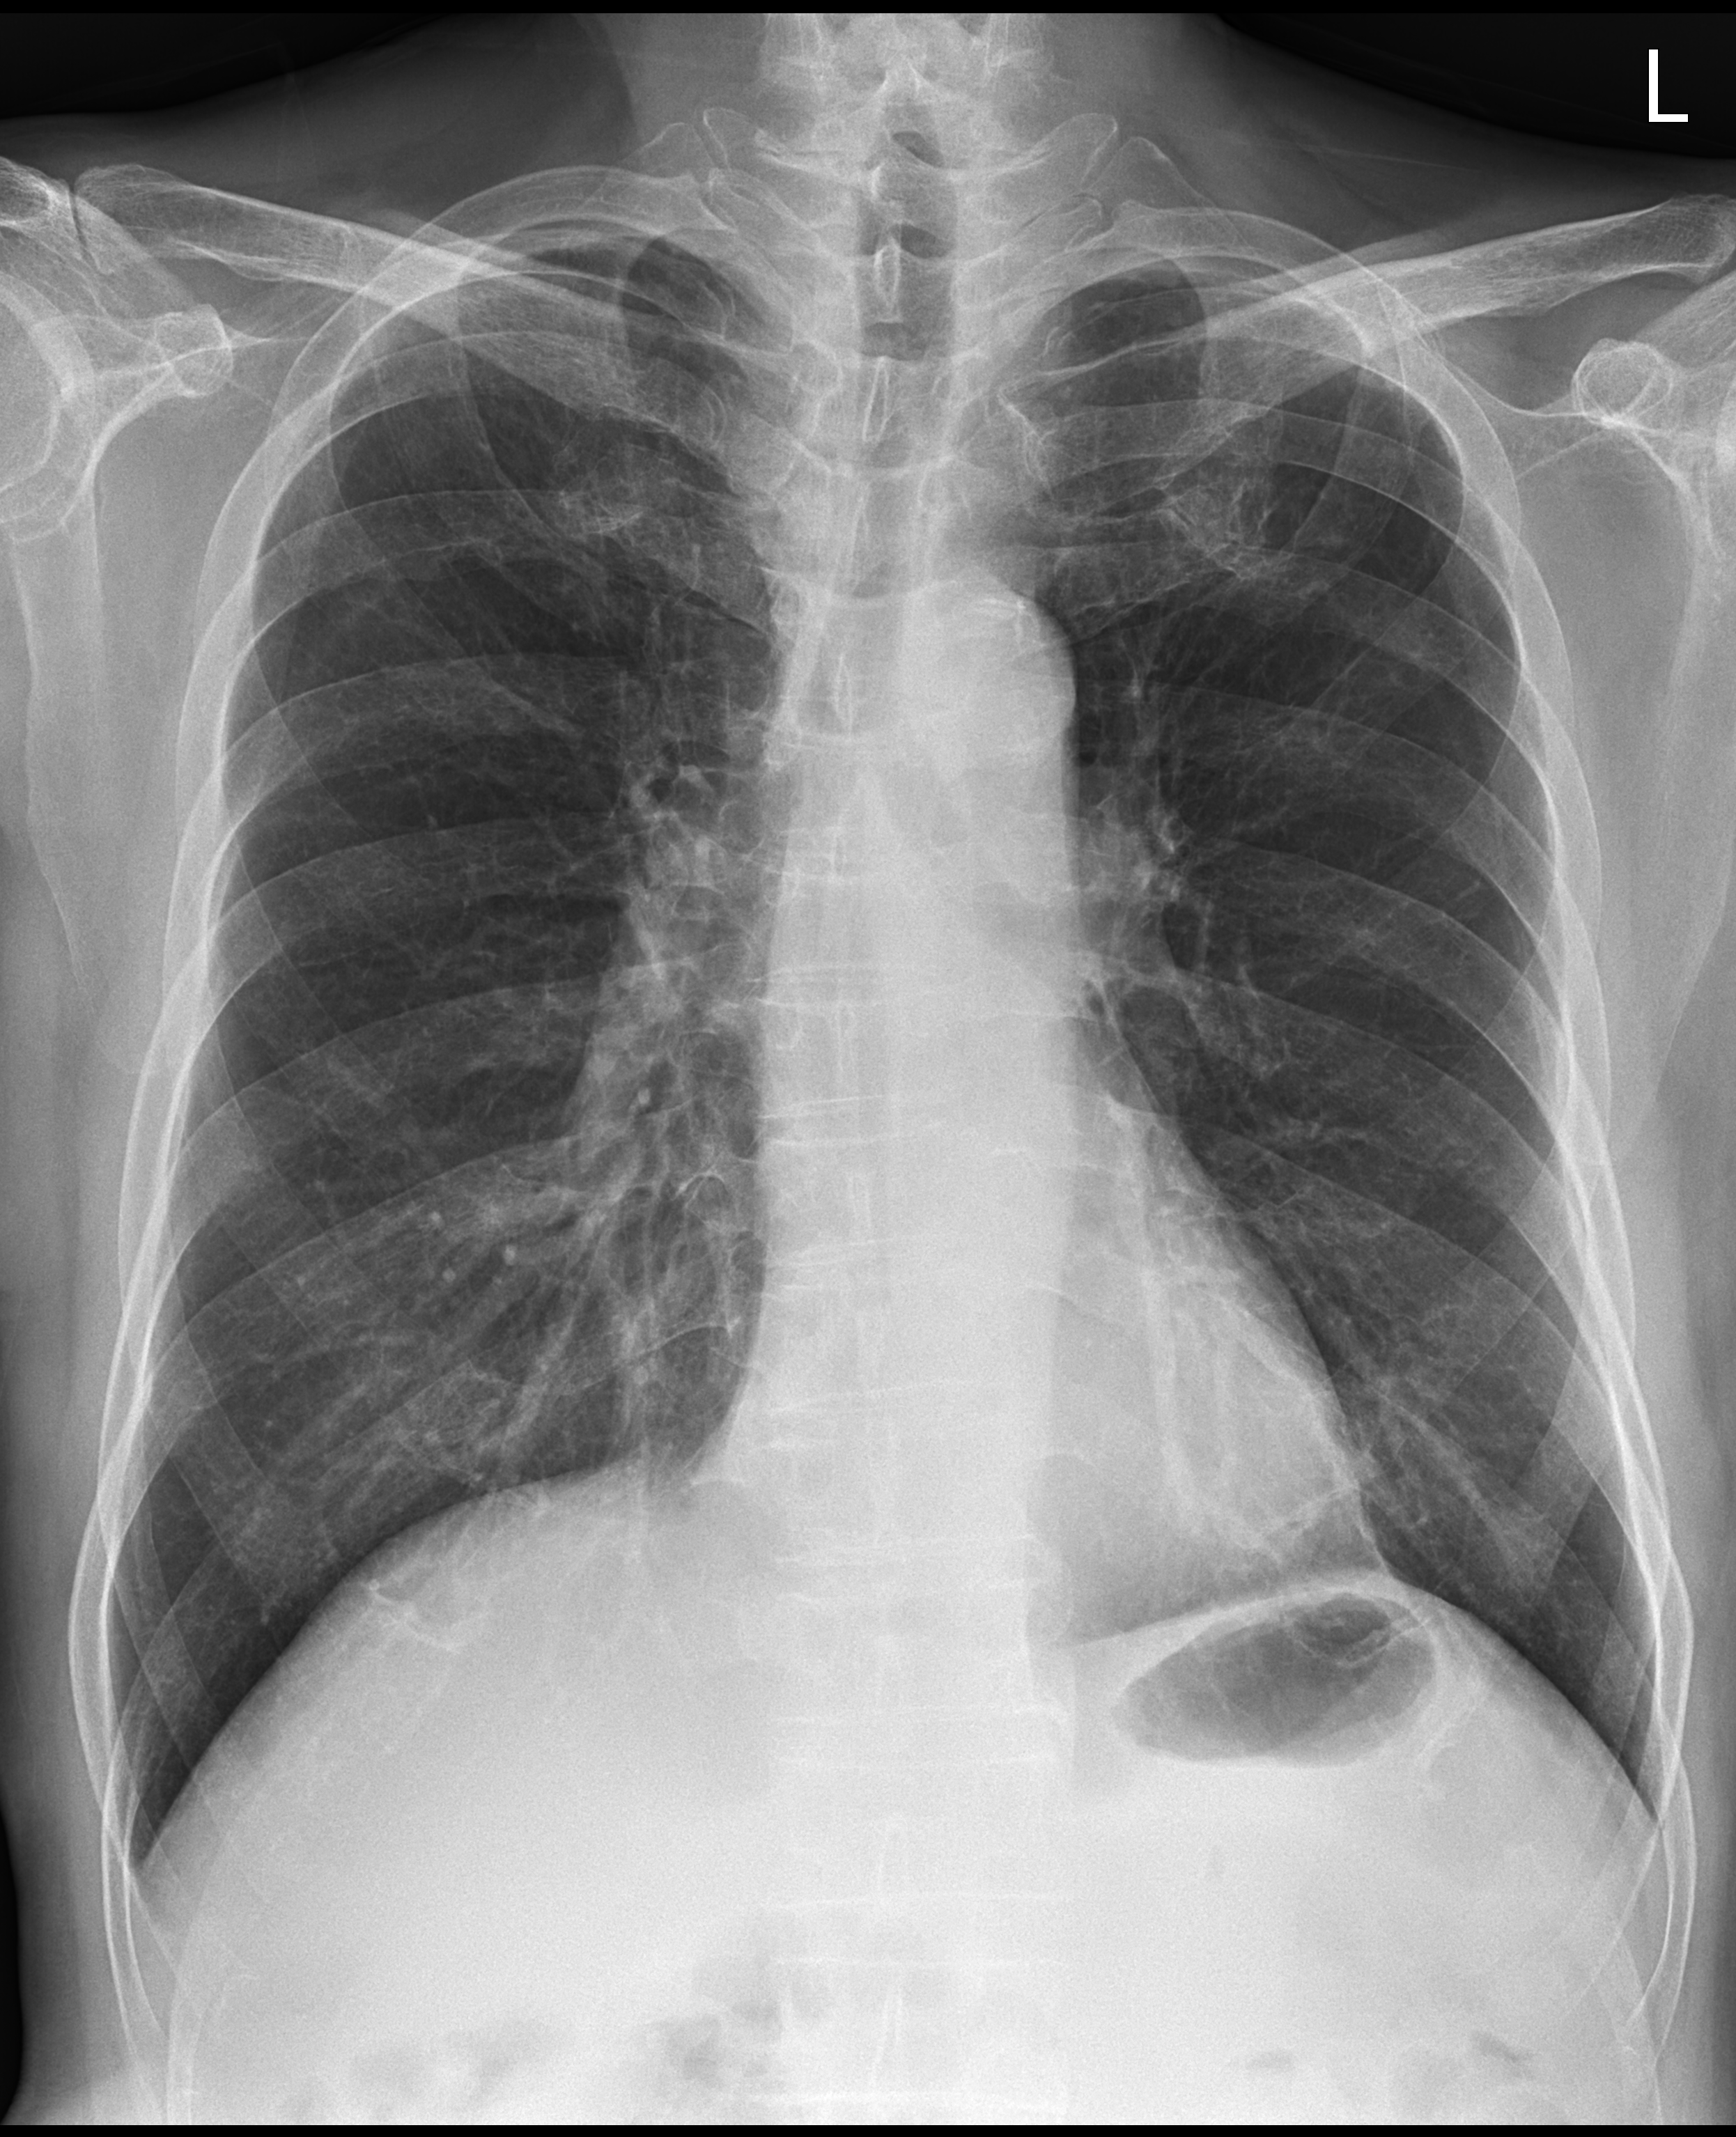

좌측의 x ray 사진은 chest PA를 오른쪽은 chest AP로 촬영한 사진이다.

한눈에 봐도 chest PA로 촬영한 것이 폐의 용적을 최대한으로 보여주기에 좀 더 선호되는 방식이고, chest AP는 환자가 서기 어려운 상황이거나 이동식 x ray 장비를 이용해야 하는 어쩔 수 없는 상황에서 촬영하는 방식이라 이해하면 편하겠다.